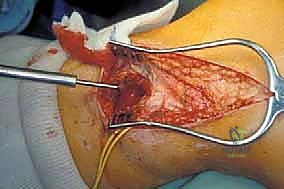

3. عزل وحماية العصب الشظوي (Nerve Isolation)

هذه هي الخطوة الأكثر دقة وحساسية. باستخدام أدوات الجراحة الميكروسكوبية، يقوم الدكتور هطيف بتحديد العصب الشظوي الشائع، وتسليكه بعناية فائقة، وإبعاده عن منطقة الورم باستخدام أشرطة مطاطية طبية لحمايته من أي شد أو قطع.

يتم تحديد الشريان والوريد الظنبوبي الأمامي والشريان الشظوي وحمايتهم. في بعض الأحيان، إذا كان الورم يحيط بأوعية دموية صغيرة، يتم ربطها وقطعها للتمكن من إزالة الورم بحرية.